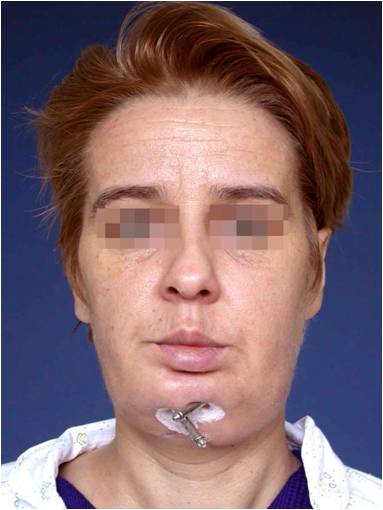

Пациент със злокачествен тумор на долната челюст наложил резекцията й. Челюстта е възстановена в последствие с помощта на дистракционна остеогенеза – случай на доц. Джоров.

Пациент с доброкачествен тумор, наложил резекция на долната челюст, при която веднага започва възстановяването й чрез дистракционна остеогенза – случай на доц. Джоров.

Лицева корекция преди и след лечението – случай на доц. Джоров